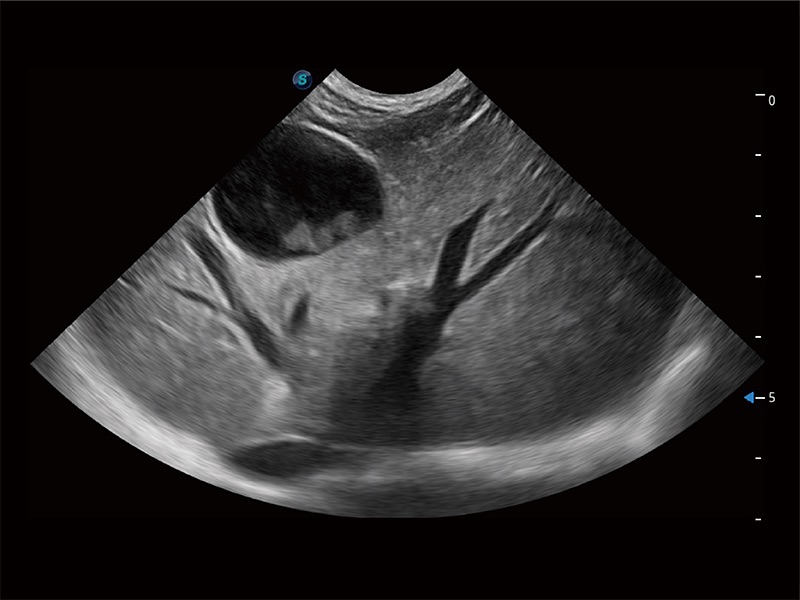

高性能和先进的临床应用工具可以为动物医生提供临床信心。ProPet 80 搭载了先进的腹部和浅表应用工具,帮助医生在日常临床实践中发挥前所未有的作用。

ProPet 80 配备了丰富的心脏探头群、先进的成像技术和专业的心脏测量工具,可帮助动物医生为不同体型和生理结构的动物提供心脏和心肌功能的全面评估。

ProPet 80 专为动物医生设计,对不同的动物体型和生理结构作出了针对性的优化。通过动物影像专用软件,可满足个性化的应用需求,帮助动物医生获得更精确的诊断数据。